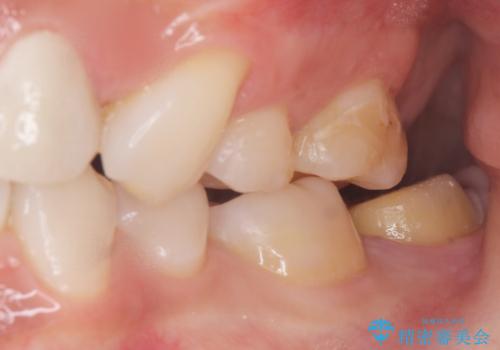

- 奥歯が黒くなっていることを気にされ来院された患者様です。

精査したところ、左下の奥歯にう蝕を認めました。

患者様のご希望により、う蝕を丁寧に除去したのちセラミッククラウンによる補綴治療を行いました。

セラミッククラウンの自然な仕上がりと咬み心地にご満足頂けました。

クラウンの種類:オールセラミッククラウン スタンダード